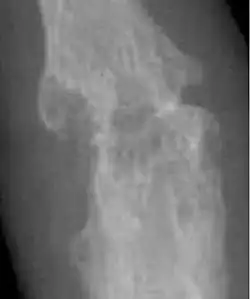

- Ankylosing spondylitis[18]

Arthritis types may also include ankylosing spondylitis, juvenile idiopathic arthritis, psoriatic arthritis, and reactive arthritis, among others.[2][6]

- Ankylosing spondylitis: 0.1% in South Africa (rural setting)